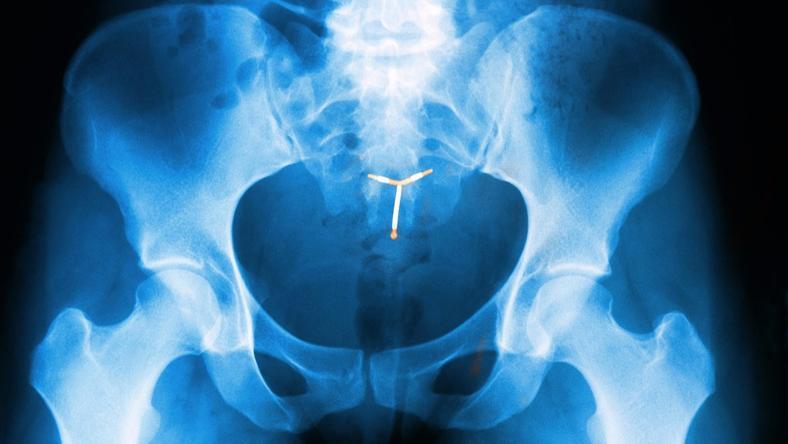

宫内节育器,就是那个中国人更喜欢称之为“节育环”的东西,有一个半指节大小,呈圆形、宫形、T 形或是其他模样,精致地包含了数重矛盾。

上世纪 70 年代开始,中国的计生政策选中了宫内节育器作为一个控制人口的重要实现方式。这个选择令这个一个半指节大小,主流为宫形或是 T 形的“装置”在这块土地上实现了最大可能的广泛使用。

在中国最初投入使用的宫内节育器是一种不锈钢圆环,刚投入使用时,它曾被认为是永久有效,不需取出。

一位 1979 年就参加工作的某县计生站站长向我描述了老奶奶那一代的“环”,“一块多钱一个,圆的,悬在宫腔中”。不锈钢圆环的问题,目前的资料看来,是失败率偏高。根据当时的数据,这种惰性圆环的脱落和避孕失败率普遍在 10% 以上,避孕有效率更强大的含铜活性宫内节育器出现后,这种不锈钢环很快就被取代了。

目前看来,这段历史的主要残迹是一个名字——环,即使在这之后的含铜宫内节育器有宫形、T 形、花形、γ 形,在人们的口中,它们都被叫做:节育环。

对于目前在中国使用最多的含铜的宫内节育器,在 WHO 的网站上将其描述为“植入子宫的小而灵活的塑料器械,含铜套管或铜线”,在那份表格中,宫内节育器的避孕效果被描述作:大于 99%。其主要不适为:“使用的前几个月常见月经时间长且量大,但不会造成损害”。